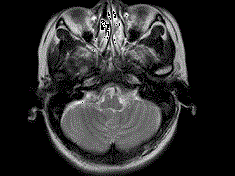

问题 女,41岁,阵发性头痛伴恶心、呕吐20余天.CT影像如图,最可能的诊断为 ( )

选项 A、双侧筛窦息真菌感染 B、双侧筛窦过敏性炎症 C、双侧筛窦炎 D、双侧筛窦未见明显异常 E、双侧筛窦息肉

答案 C